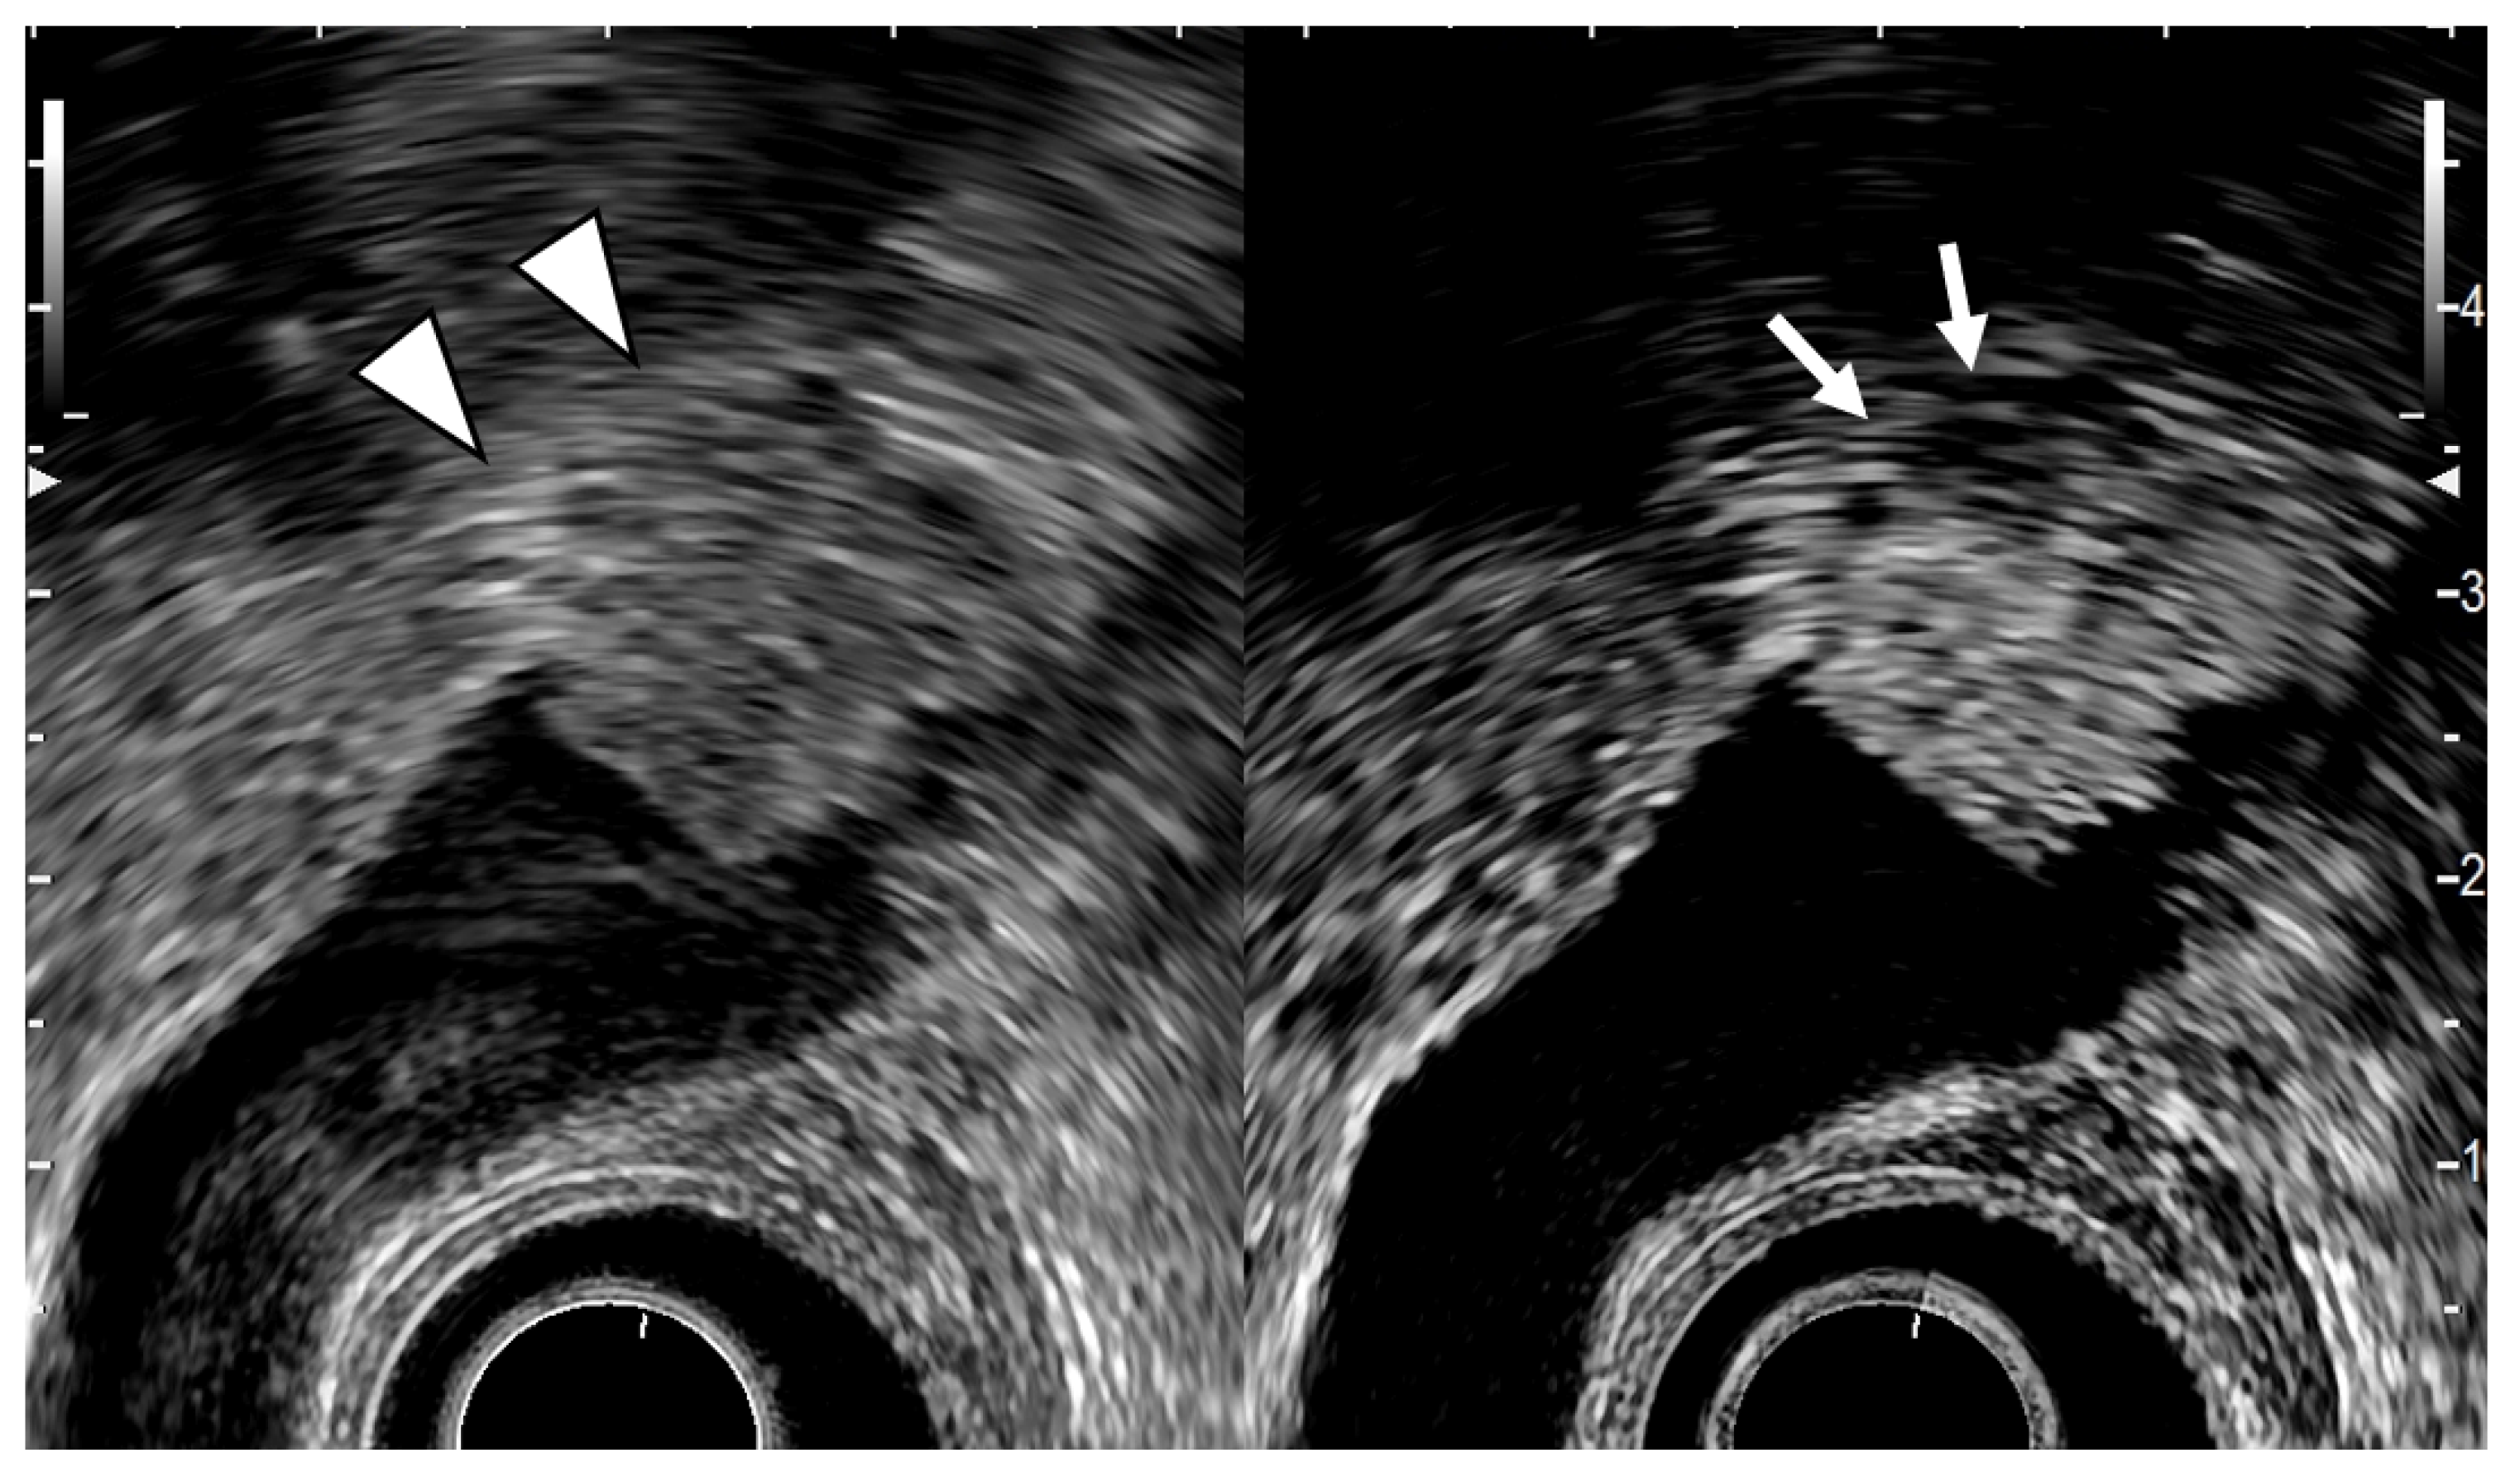

Fujita et al. [49] classified EUS images into four categories: type A, a pedunculated mass with a finely nodular surface and without abnormality of the neighboring gallbladder wall; type B, a broad-based mass with an irregular surface and no disruption of the outer hyperechoic layer of the gallbladder wall; type C, irregularity of the outer hyperechoic layer due to mass echo; and type D, disruption of the outer hyperechoic layer by mass echo (Figure 6). They then assigned the image types EUS to T stages for GB carcinomas. Type A would be a tumor in situ (Tis); type B, T1 or possibly T2; type C, T2; and type D, T3 or higher. Each of the four EUS image categories correlated well with the histologic invasion depth (Table 5).

Figure 6.

EUS image of GB carcinoma. The conventional EUS (left) shows that a broad-based elevated lesion is found at the fundus of the GB with hypoechoic (arrowhead) in the deep part of the lesion and rupture of the lateral hyperechoic layer. In the contrast-enhanced EUS (right), the contrast effect of most of the lesion is good, but the deep part of the lesion is poorly contrasted (arrow). It can be diagnosed from these findings as GB carcinoma with invasion depth T3a (SE).

6. Contrast-Enhanced EUS

Another study by Imazu et al. [53] using contrast-enhanced EUS in the differential diagnosis of GB wall-thickening demonstrated inhomogeneous enhancement as a strong predictive factor of malignant GB wall-thickening (Figure 8). The same study reported that overall sensitivity, specificity, and accuracy for diagnosing malignant GB wall-thickening for EUS and contrast-enhanced EUS, respectively, were 83.3% versus 89.6%, 65% versus 98% (p < 0.001), and 73.1% versus 94.4% (p < 0.001).

Figure 8.

EUS image of GB carcinoma. Irregular wall-thickening of the GB (arrowhead) is observed. In the conventional EUS image (right), a structure is found inside the GB and the lumen is unknown. The contrast-enhanced harmonic image 21 s after the injection of Sonazoid® (left) shows heterogeneous enhancement in the thickened wall (arrowhead). The structure inside the GB is not enhanced and can be diagnosed as biliary sludge (arrow) rather than a neoplasm.